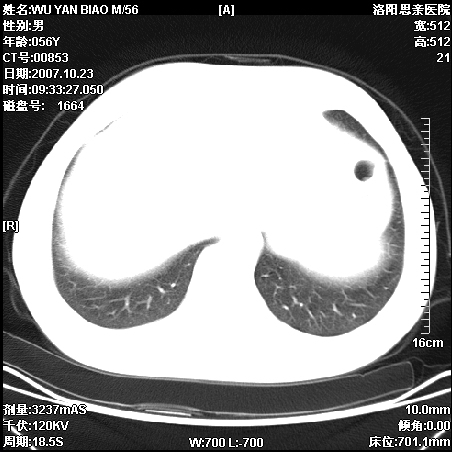

标题: CT10160:M56Y,体检发现,病人无不适,病人随访中 [打印本页]

标题: CT10160:M56Y,体检发现,病人无不适,病人随访中

后上纵隔占位,与肺交界清,宽基底附着脊柱,密度均匀,局部骨质无明确改变.

考虑;神经源性肿瘤,---起源交感n链?,不除外肠源性囊肿.

1、病灶在后纵隔脊柱旁沟内,此处是神经原性肿瘤的好发部位

2、病灶边缘光滑整齐,更说明病灶来于纵隔,由于有胸膜的包裹所以才导致这么光滑的边缘

3、病灶内的密度均匀